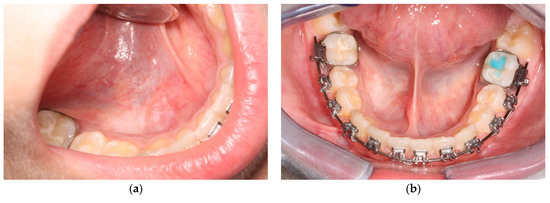

2. Materials and Methods